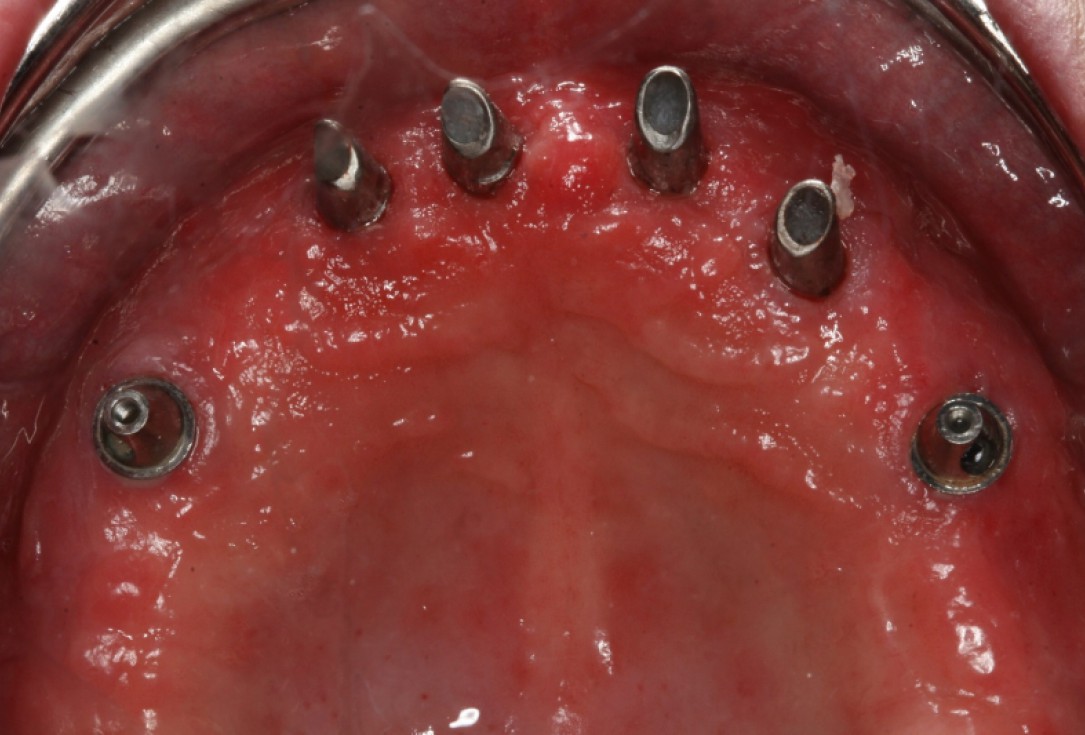

Surgical presentation of the alveolar ridge with reduced amount of horizontal bone available